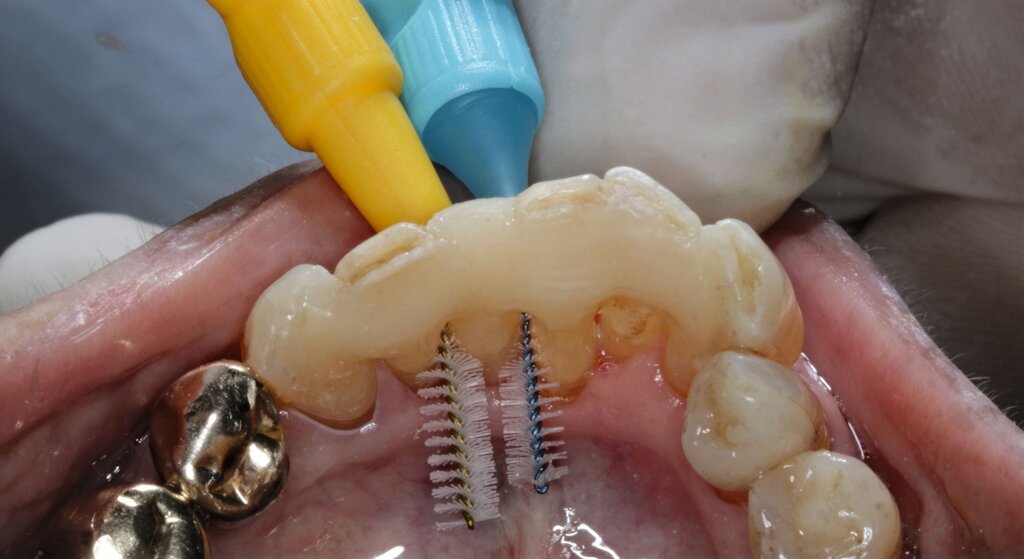

Um bei der adhäsiven Befestigung des Kunststoff-Prothesenzahns das Risiko einer Speichelkontaminierung zu reduzieren, wurde Kofferdam verwendet. Die Interdentalräume wurden mit einer elastischen Befestigungsschnur (Wedjets, Coltene) blockiert, um ein späteres Ausfließen der Interdentalräume mit Komposit zu verhindern – einerseits um weiterhin eine gute häusliche Mundhygiene zu ermöglichen, andererseits um keine unnötig langwierige Nacharbeitung bei der Entfernung von überschüssigem Komposit zu verursachen (Abbildung 9).